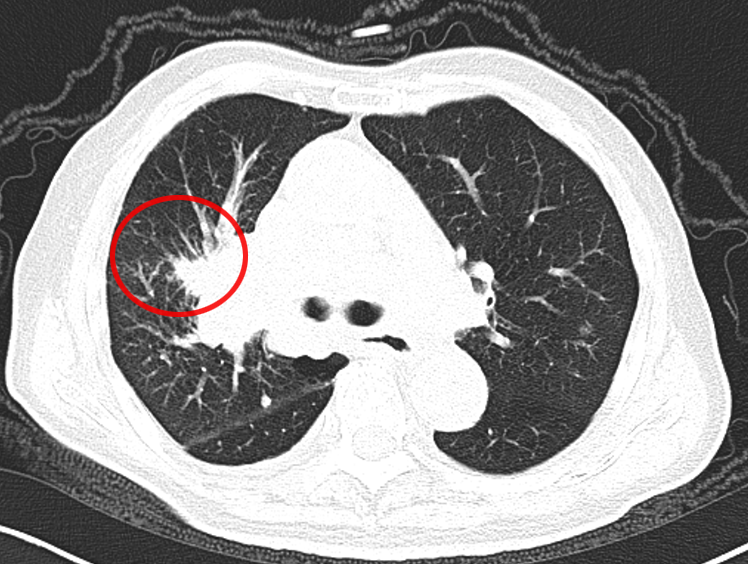

还有另一位患者,肺部结节只有 15mm,还合并了空洞,医生同样通过 CT 引导精准定位,成功完成经皮肺穿刺取到病理组织,最终诊断为 “腺癌”(免疫组化提示 CK7、TIF-1、NapsinA 阳性,排除其他类型肿瘤)。

什么是 CT 引导下经皮肺穿刺?

它就像一位精准定位的 “远程射手”:在 CT 的 “透视眼” 帮助下,医生能清晰看到肺部病变的位置、大小,以及周围的血管、气管等结构;随后用一根细针,从胸壁皮肤轻轻穿刺进入肺部,直达病变部位,抽取少量组织送检。

这种方式尤其适合深部或微小病灶—— 比如位置藏得深、体积小到 1cm 左右的病灶,CT 引导几乎是实现精准穿刺的唯一选择,能帮医生在不 “大动干戈” 的情况下明确肿瘤身份。